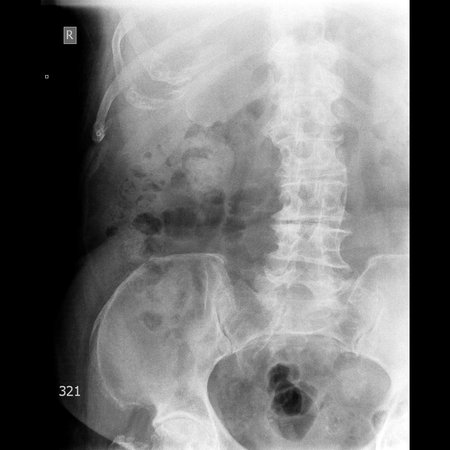

Фарфоровый желчный пузырь (Porcelain gallbladder)

Женщина средних лет без жалоб на здоровье.

Еще случай.

Бабушка из отделения сестринского ухода, без жалоб на боли в животе. Лаб. анализы не изменены.

Если кальциноз стенки полный и содержимое пузыря осмотру не доступно, то есть показания к проведению КТ-МРТ. Если стенки инкрустированы частично (как в представленных случаях) и можно оценить характер содержимого и структуру стенок, то можно ограничиться только УЗИ. Далее, если есть подозрение на опухоль то пациента направляют к онкологу, а он сам определяет дальнейшую тактику.

Это форма хронического холецистита с кальцификацией стенки ЖП. Термин "фарфоровый" отражает голубоватый оттенок и хрупкую консистенцию ЖП. У мужчин возникает в 5 раз чаще. Кальцификация стенки представляет собой либо непрерывную кальцификацию мышечного слоя, либо прерывистую кальцификацию слизистой и подслизистой. У таких больных высока частота возникновения рака ЖП (11-33%) Каждый раз, когда при УЗИ имеется подозрение на фарфоровый ЖП, для подтверждения диагноза и оценки степени злокачественности проводят КТ